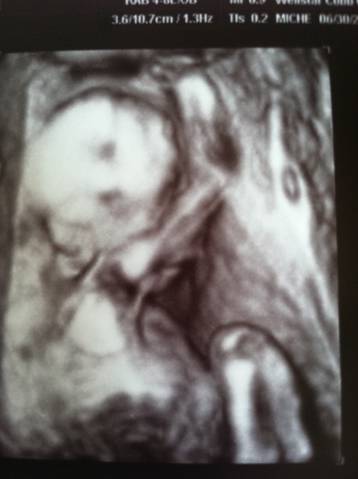

It is now 1:19 pm and we just got home from our doctor appointment! Neither of us has stopped smiling since hearing the wonderful news. Our little one is healthy, heart beating at 150 beats per minute, and all of the measurements are perfect. We can’t make the big announcement quite yet though… We want to make sure our families get first priority. We will be posting pictures and videos and make the big announcement as soon as we have talked to all immediate family. 🙂 It is measuring at 20 weeks, 6 days, so baby is just a few days older than what we originally thought. We love y’all and stay tuned- we can’t wait to share our news.